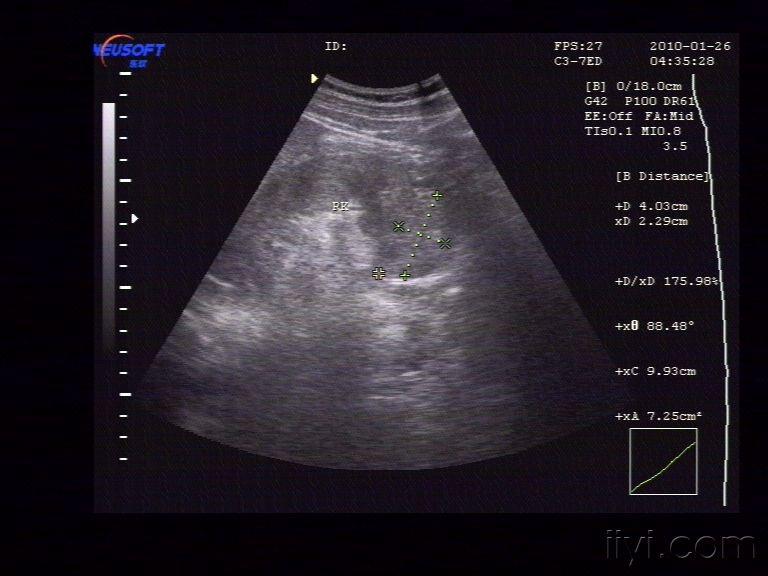

右肾挫伤,肾盂积血 - 超声医学讨论版 - 爱爱医医学论坛

图片尺寸768x576